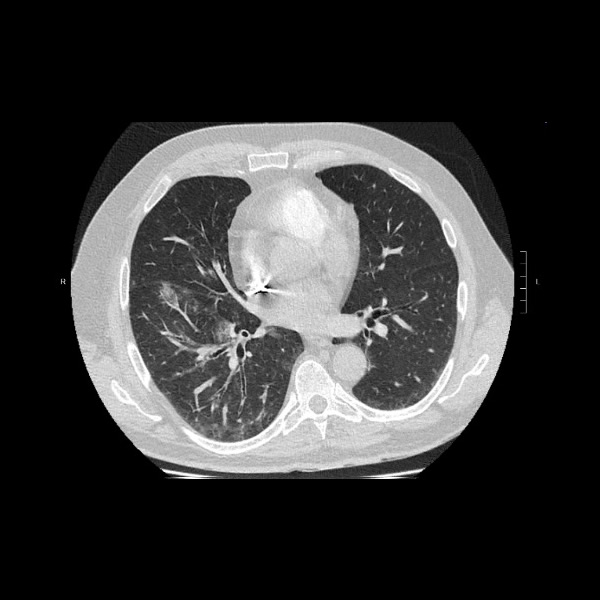

Hemoptisis